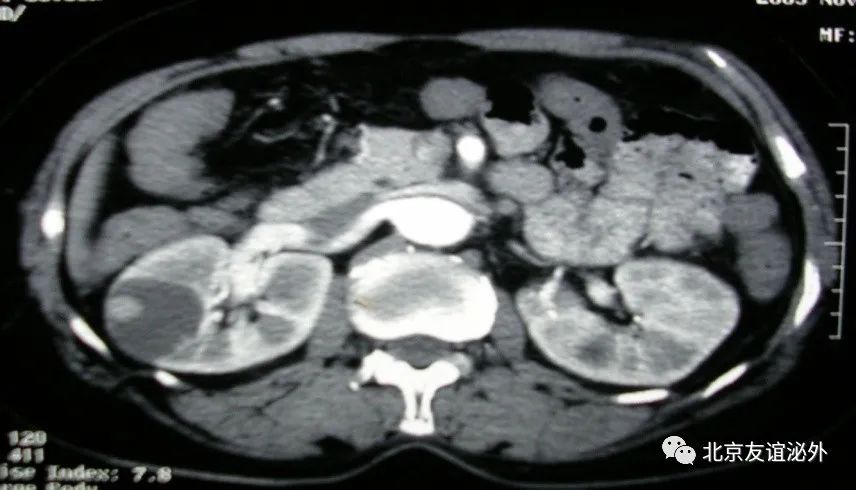

肾囊肿通常根据CT或核磁等影像学检查分为Bosniak I, II, IIF, III, and IV级,通常I级和II级被认为是单纯囊肿,而其他被认为是复杂囊肿,随着级别的增高,囊肿的恶性可能也在增加,I, II, IIF, III和IV级的恶性可能分别为0-1%,0-10%,4.7-24%,>50%和>90%。如果囊肿中出现不规则增厚的分隔、不规则增厚的囊壁、囊肿内部不均质、尤其出现可增强的囊内结节、厚壁分隔和囊壁需要密切关注,应及时就医。

图1. Bosniak I级良性囊肿,是临床上最常见的囊肿